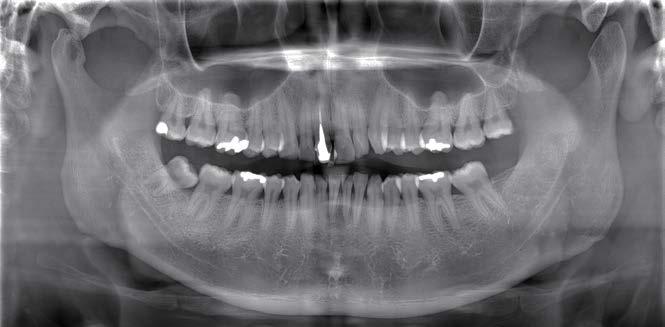

Klinisches Fallbeispiel

Die Panoramaaufnahme zeigt einen horizontal impaktierten Eckzahn im linken Unterkiefer. Eine weitere Untersuchung einer 3D-Aufnahme ergibt einen Zusammenhang zwischen dem impaktierten Zahn und den vorderen unteren Schneidezähnen. Ferner lässt sich ein Zahnsäckchen erkennen, was auf eine vorhandene Dentitionszyste hindeutet.